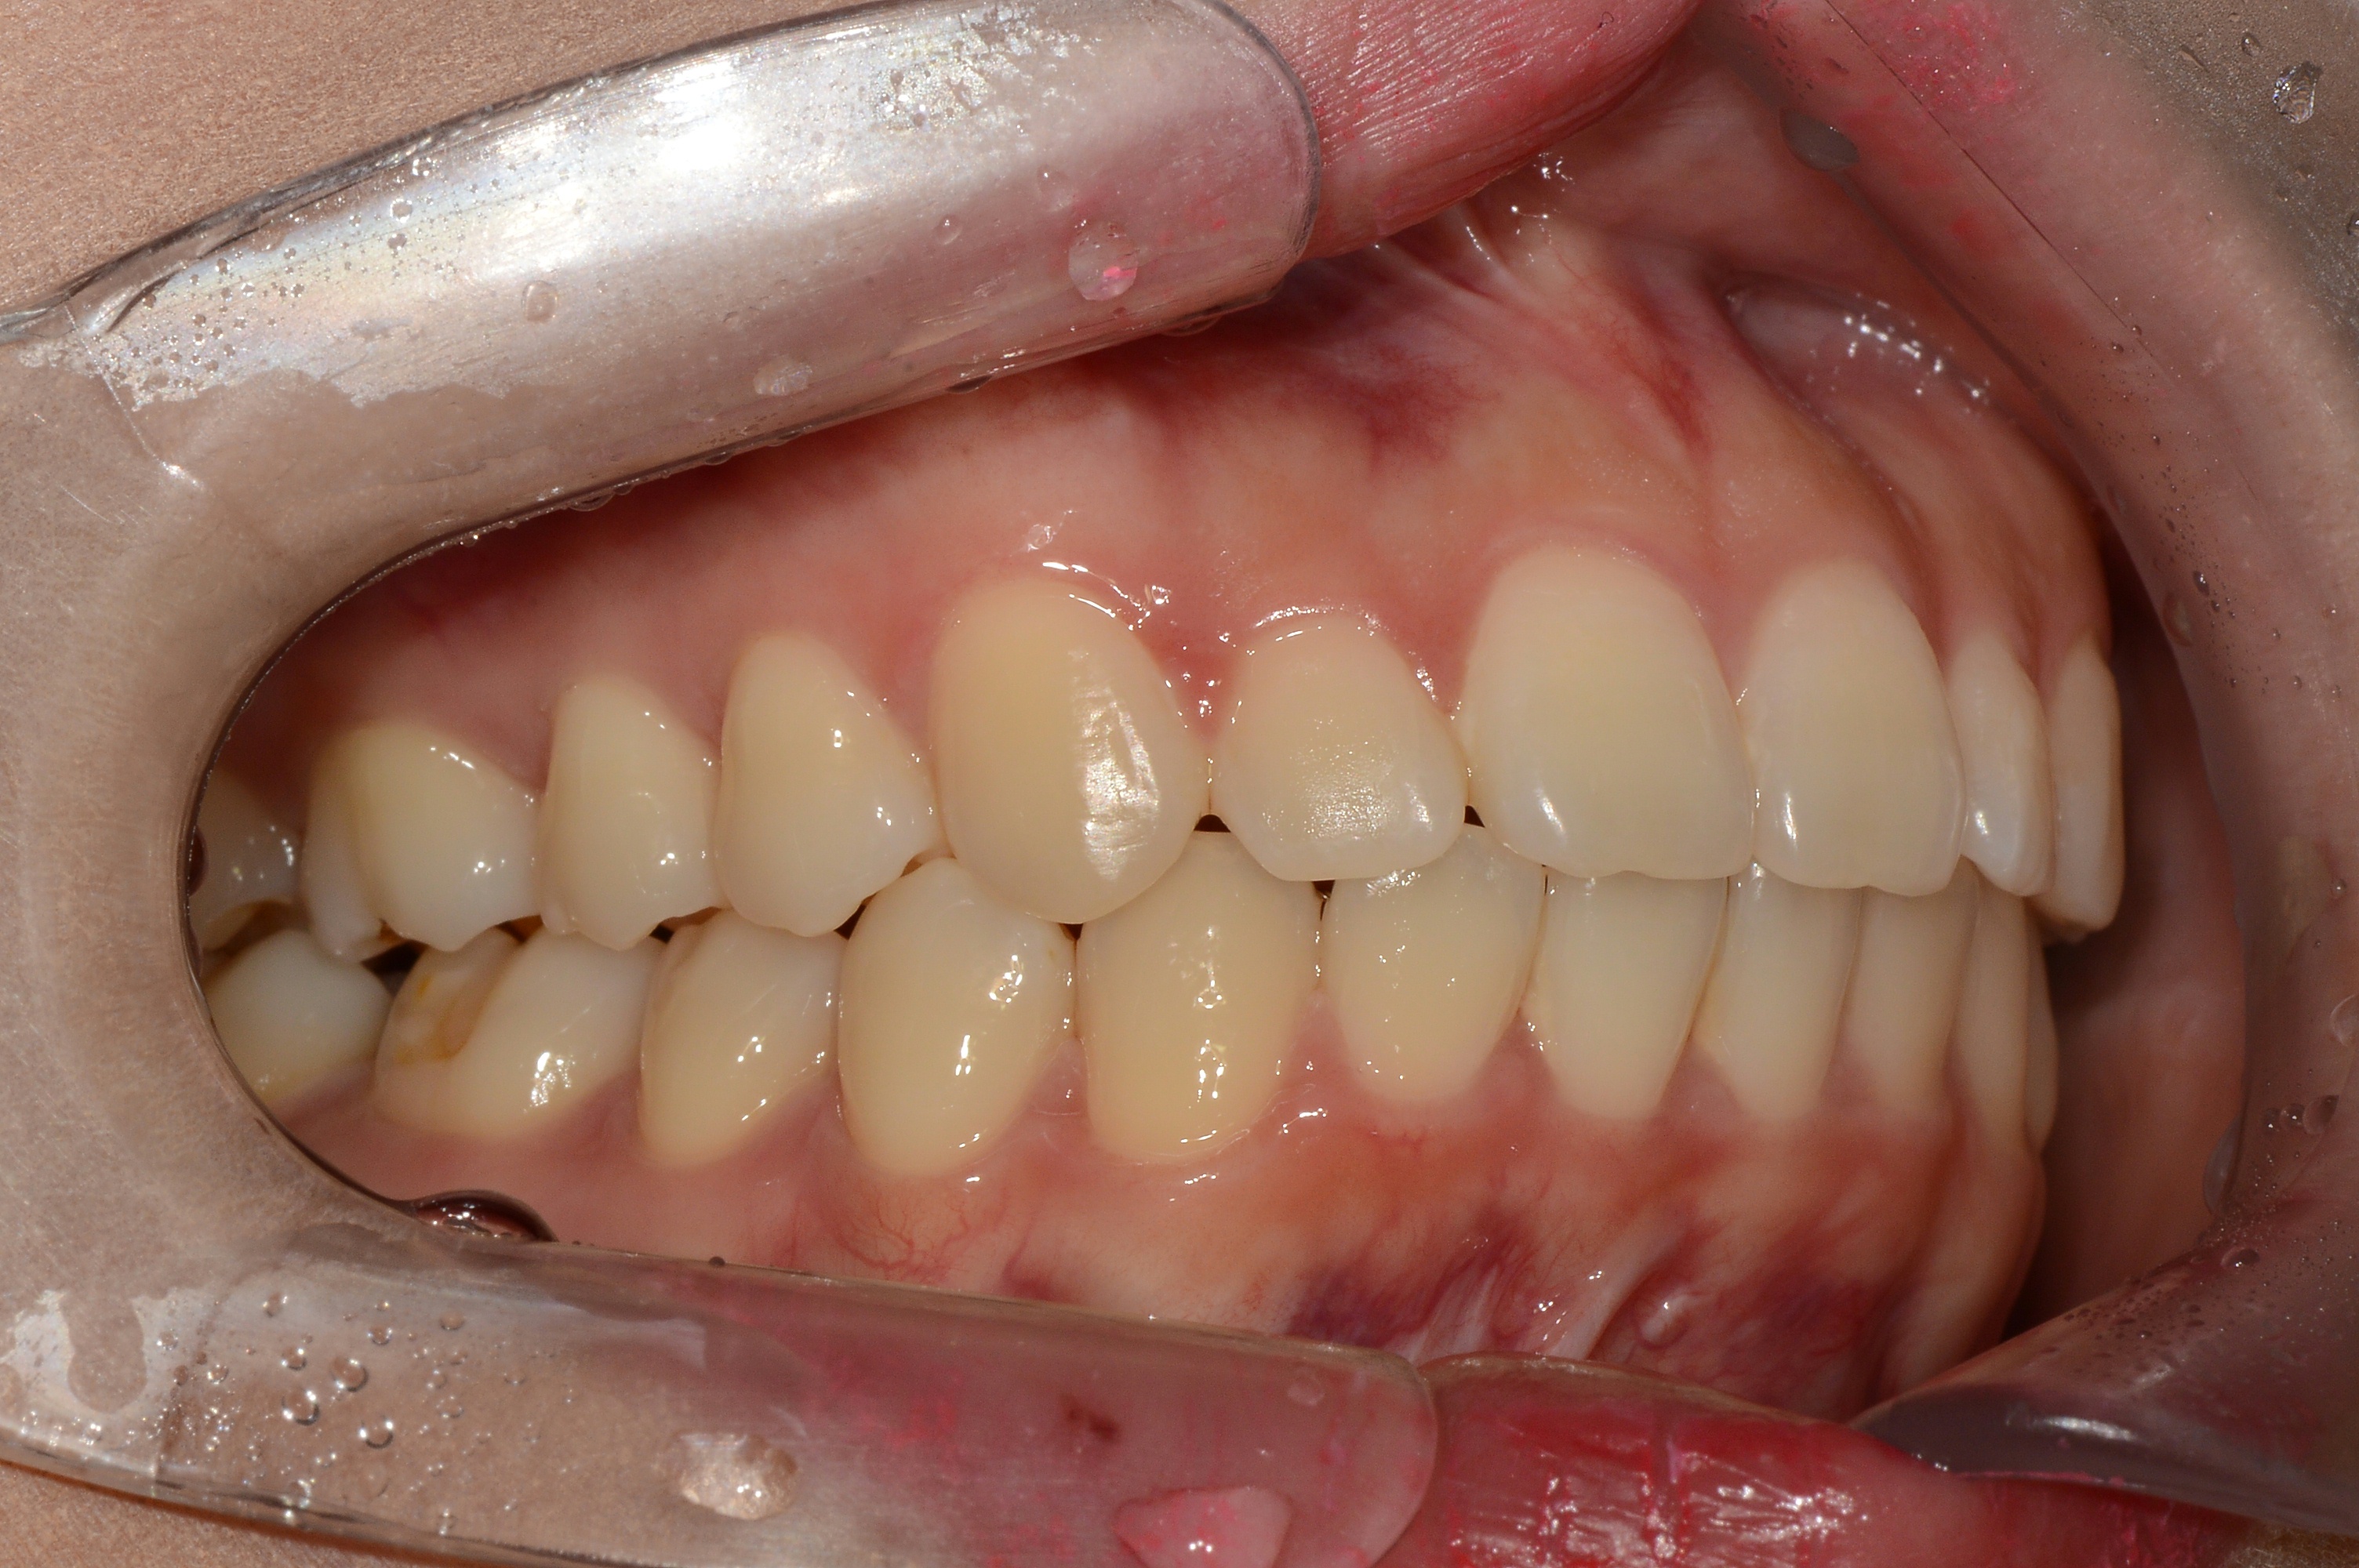

치료 전 사진입니다.